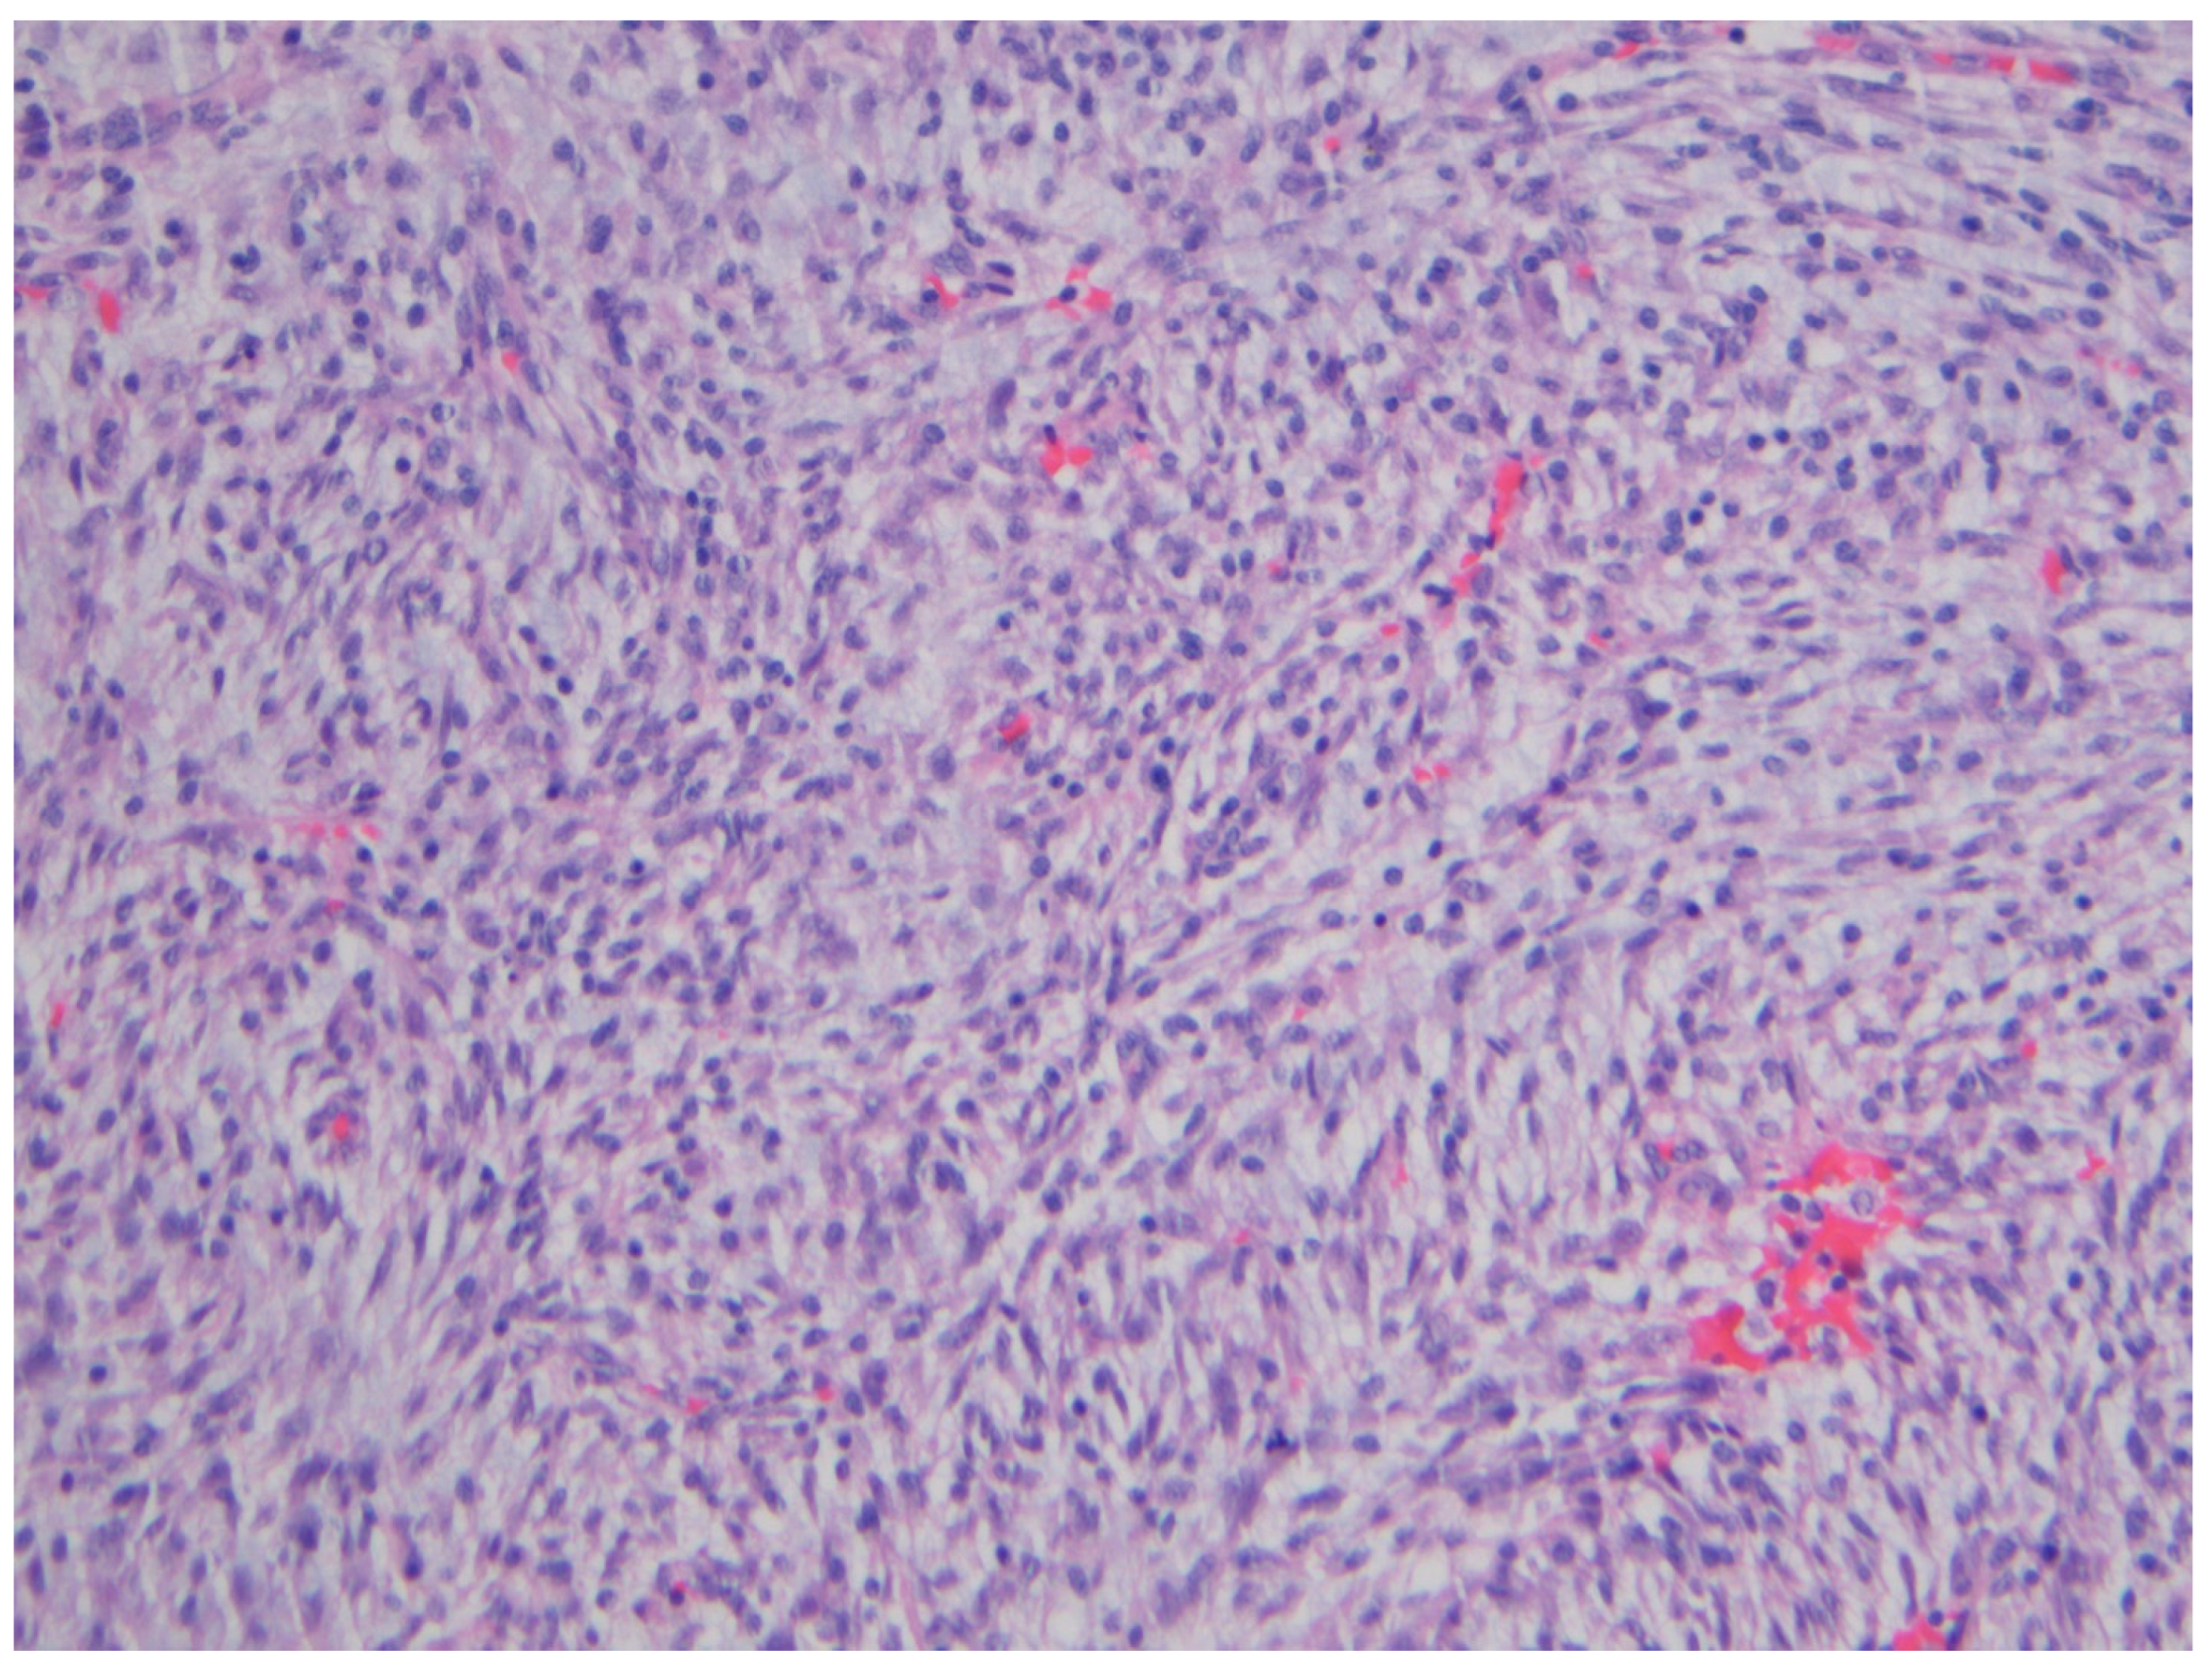

| Inflammatory myofibroblastic tumor | Children and young adults | Colon and small intestine | Variable, from abdominal pain to obstruction | Uniform, plump spindle cells with pale cytoplasm organized into loose fascicles; colagenous or myxoid stroma with inflammation, mainly lymhocytes and plasma cells | α-SMA, ALK positive |